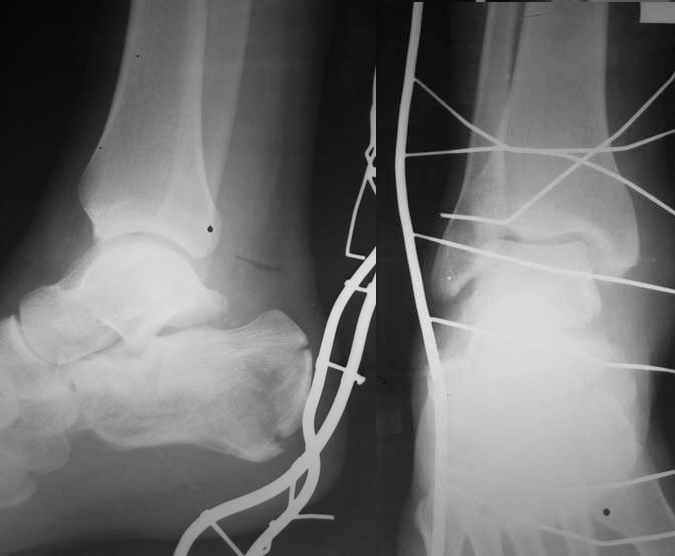

представляю снимки пациента с переломом пяточной кости. послеоперационный снимок этапный - по снятии швов спицы удаляю и наладываю циркулярную гипсовую повязку. к сожалению снимки с удаленной скобой представить не могу но поверьте на слово - консолидация полная, коррекция стойкая.

при планировании операции и ее исполнении выполнена костная аутопластика трансплантатом с гребня подвздошной кости причем трансплантат брался фрезой размером несколько болишим чем образованный в результате травмы дефект. скоба в данном случае обеспечивает компрессию между отломками-трансплантатом